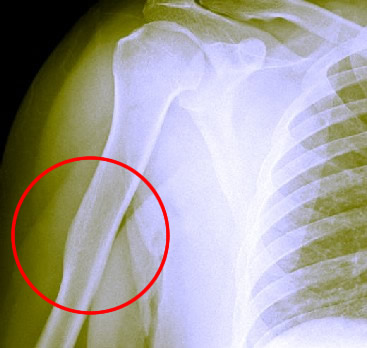

A Healed Humerus Bone. Other Than the Slight

Deformity,The Bone Looks Fairly Uniform